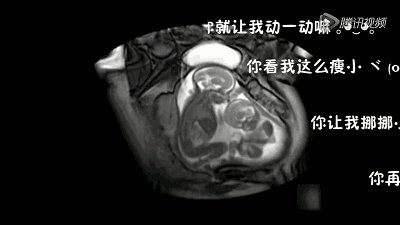

那天看到宁夏双胞胎在肚子里打架的视频,感觉特别可爱,这对双胞胎已经平安出生,

具体是这样的,一个怀有双胞胎的孕妇去做产检时,发现两个孩子在打架,你一拳我一拳,推推搡搡,嘴里好像念念有词,战斗了几个回合不停止,把在场的人引得哈哈大笑。

我也看到了这样的小视频,看起来蛮有意思的,两个宝宝在妈妈肚子里旋转、跳跃,当妈的也乐开花了。